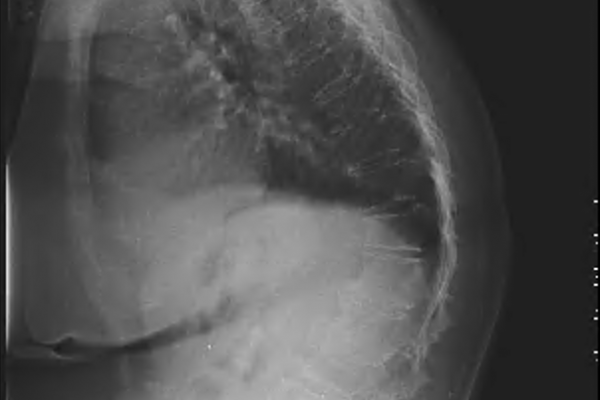

KAMBURLUK VE OMURGA EĞRİLİĞİ (KYPHOSCOLİOSİS)